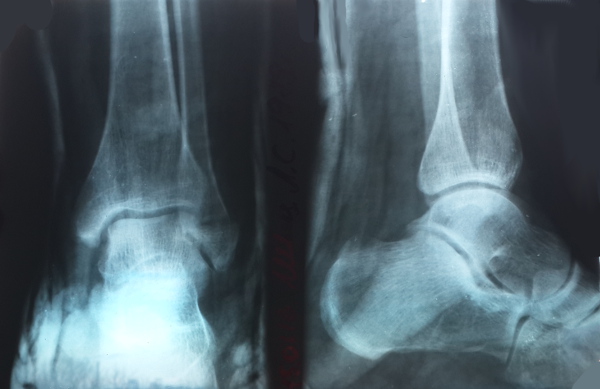

Врачи отмечают, что рентгенография голеностопного сустава является важным методом диагностики, позволяющим выявить различные патологии, такие как переломы, вывихи и артриты. Процедура начинается с подготовки пациента: ему объясняют, как будет проходить исследование, и просят снять все металлические предметы, которые могут помешать получению качественного изображения. Затем пациент занимает удобное положение, обычно сидя или стоя, и ставит ногу в специальный аппарат. Врачи подчеркивают, что важно сохранять неподвижность во время съемки, чтобы избежать размытия изображения. Рентгеновские снимки позволяют специалистам детально оценить состояние костей и суставов, что способствует правильной постановке диагноза и выбору оптимального лечения.

Специалист объясняет пациенту, как правильно расположиться относительно рентгеновского аппарата. Обычно требуется сделать снимки в двух проекциях, а также третий под углом, поэтому пациенту придется несколько раз менять позу.

- Стандартный метод используется в большинстве случаев. Он включает получение изображений в двух проекциях (спереди и сбоку). В некоторых случаях могут назначаться менее распространенные методы. Снимки могут быть сделаны сзади и спереди, только со стороны стопы или под углом (косая проекция). При наличии артрита делают снимки обеих конечностей — здоровой и пораженной.

Рентгенолог анализирует снимки, основываясь на выявленных отклонениях от нормы и видимых дефектах костной структуры.

Диагноз формируется на основе данных рентгеновского снимка. При подозрении на плоскостопие учитываются высота и угол свода стопы.

На рентгенограмме также хорошо видны другие заболевания костных тканей.

Если метод диагностики не предоставляет полной информации, пациента направляют на дополнительные обследования. Например, при подозрении на перелом голеностопного сустава рентген может не дать четкого представления о степени повреждения.